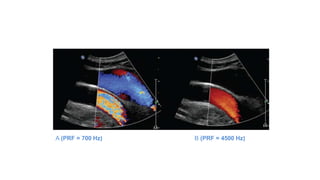

A (PRF = 700 Hz) B (PRF = 4500 Hz)

Aliasing of the spectral Doppler display is characterized by "wraparound“

of the highest velocities to the opposite direction when the sampling (PRF)

is inadequate. Right: Without changing the overall velocity range, the

spectral baseline is shifted to incorporate higher forward velocity and less

reverse velocity to avoid aliasing. The maximum, average, and minimum

spectral Doppler display values allow quantitative determination of

clinically relevant information such as pulsatility index and resistive index.